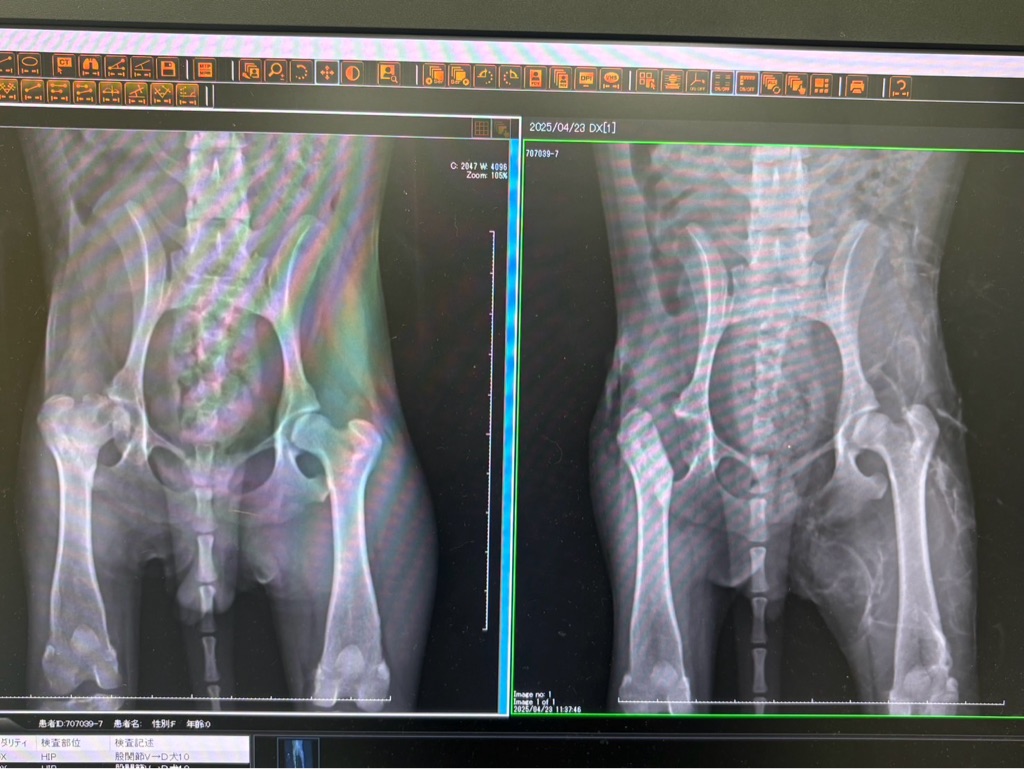

先日2匹はシェルターで手術を終わらせて下さって

4匹はER八王子病院で預かって頂き今日手術をして下さいました。

すごいです👍 次々とパテラので手術が終わりました😆